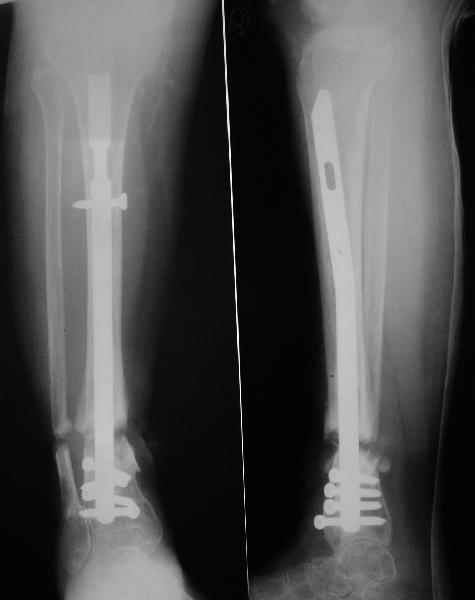

Аппарат - чтобы плавно исправить ось. В приложении - снимки на момент окончания коррекции в аппарате, фото с операции, и послеоперационная рентгенограмма.

Диаметр гвоздика 10,5 мм. Пришлось укорачивать до 23 см - уж очень миниатюрная дама, отверстия насверлил под 45 градусов, под 5 мм винты. По оси удалось сблизить до этого положения. Заперли гвоздь пока статически с планом через 2 месяца верхний винт убрать. Но это ей придется уже в Ташкенте сделать. Что скажете? Спасибо.

In attachment - x-rays at the end of alignment, the surgery, and result. The nail was cut to 23 cm. Four 45 degree holes were pre-drilled at the distal nail tip. The nail was locked statically

after some impaction. Dynamization is considered in 8 weeks. Any comments/critics?

А вдруг там все-таки от дистракции образуется регенерат, хоть дохленький? На созревание и зарезервировали 2 месяца стабилизации.

Если регенерата совсем не будет - после отпирания гвоздя отломки начнут сближаться до полного контакта. А если все-таки будет - еще и ~1 см выиграем.

NL> If you dynamise before regenerate maturation, d'ont you loose lenght?

Sure. Frankly speaking the target was just functional stable aligned limb regardless of shortening. I don't expect regenerate appearance, but what if i am wrong? If the bonus appears in the gap, we'll give it 2 month to mature. Anyway x-rays will be taken prior screw removal so dynamization can be postponed if necessary.